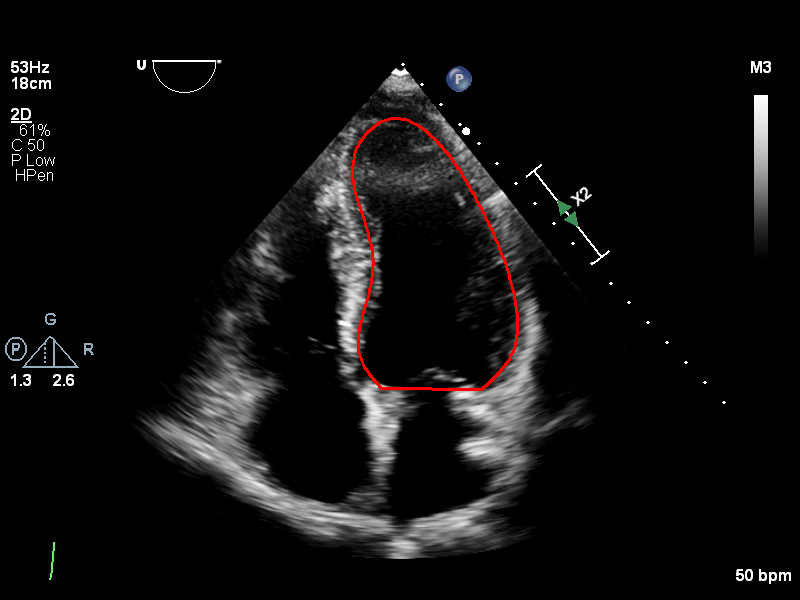

The image on the left illustrates an example of the multi-expert annotations within this dataset, while the corresponding consensus curve is shown on the right.

The Unity web-based, interactive, real-time annotation platform enables clinical experts across the UK to collaboratively and efficiently label medical images. The platform’s intuitive interface allows experts to annotate key anatomical structures with precision, including critical features such as key points and curves along the endocardial border, as illustrated above. The platform’s accessibility and real-time capabilities facilitate large-scale multi-expert annotations, enhancing the quality and accuracy of labelled datasets for medical image analysis.